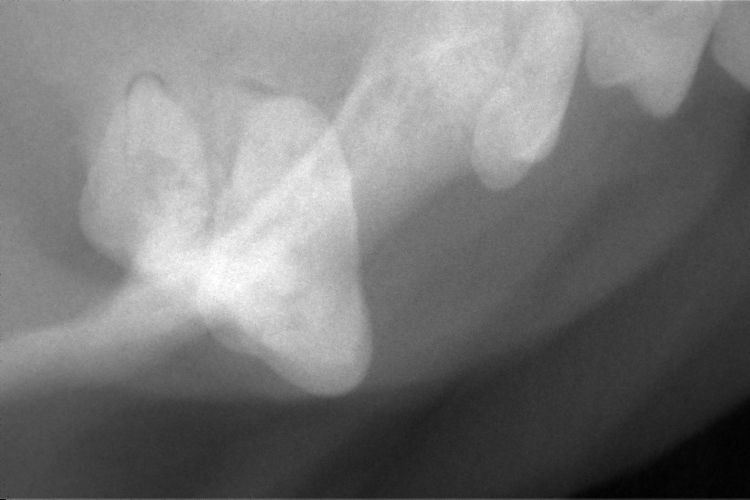

歯科レントゲン

下顎切歯部分です。

右下顎第2切歯が歯根破折していました。(黄色〇部分)

歯肉の発赤があった右上顎第4前臼歯です。

歯根部の異常は確認されませんでした。